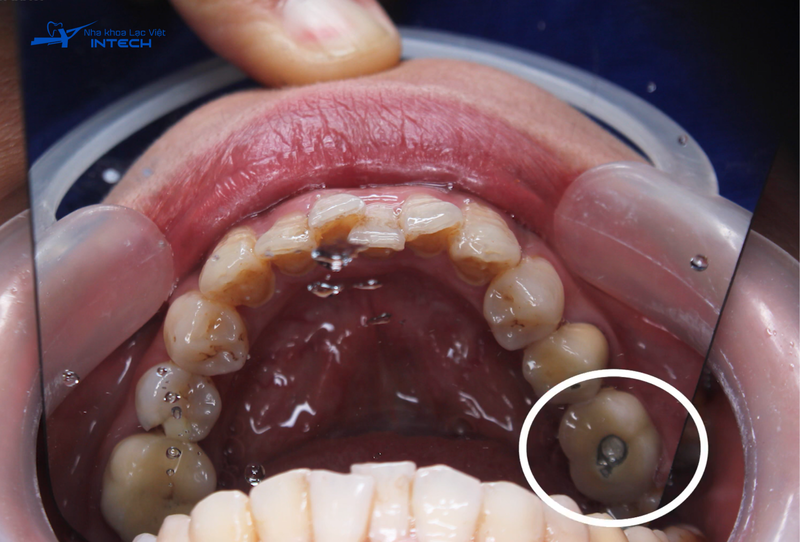

Trường hợp Implant ở vị trí răng hàm

Trong trường hợp người muốn niềng răng đã trồng răng Implant ở vị trí răng hàm và Implant được đặt đúng vị trí, không ảnh hưởng đến quá trình dịch chuyển của các răng thật, bác sĩ có thể niềng răng ngay sau khi thăm khám. Quá trình niềng răng sẽ không yêu cầu tháo mão răng, vì Implant đã ổn định và không cản trở sự di chuyển của các răng xung quanh.

Lúc này, trồng răng implant răng hàm sẽ đóng vai trò như một điểm neo chặn vững chắc tương tự như các minivis chỉnh nha, giúp kéo lùi các răng thật ở phía trước về đúng vị trí mong muốn. Phương pháp này không chỉ giúp cải thiện khớp cắn, thẩm mỹ mà còn đảm bảo quá trình niềng răng diễn ra an toàn và hiệu quả, không ảnh hưởng đến chất lượng của răng Implant.

Hình ảnh răng Implant được cắm tại vị trí răng hàm